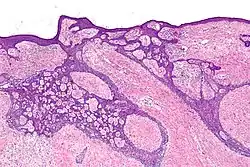

| Fibroepithelioma of Pinkus | Anastomosing epithelial strands in a fenestrated pattern[34] | Most commonly occurs on the lower back.[30]: 748 [31]: 648 |

|

![Fibroepitheliomatous pattern (anastomosing basaloid epithelial strands enclosing round islands of fibrous stroma)[36]](./Micrograph_of_basal-cell_carcinoma_with_fibroepitheliomatous_pattern.jpg)